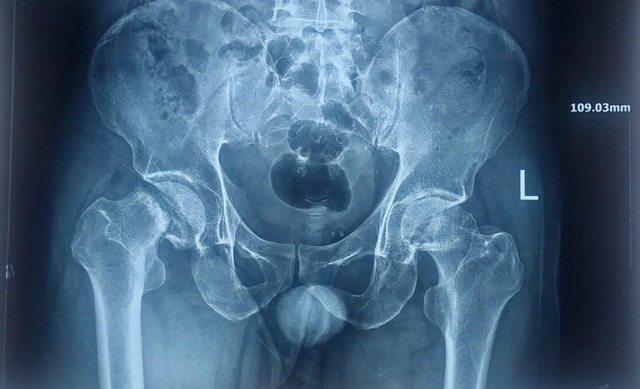

Hình ảnh X-quang trước phẫu thuật cho thấy bệnh nhân bị hoại tử nặng chỏm xương đùi 2 bên

ẢNH: ĐT